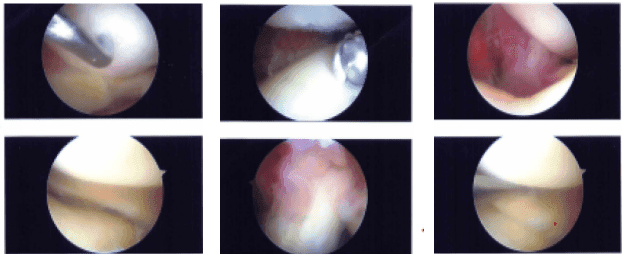

A lateral anterior portal was made and the arthroscope was inserted. A medial anterior portal was made using a spinal needle. Examination of the medial tibial compartment showed a radius tear of the posterior body of the posterior horn of the medial meniscus.

Resection of the margins of the tear was performed with the use of biters and shavers which achieved balanced margins. There was a horizontal tear also which was debrided. Balanced margins would be achieved. There was Grade III to Grade IV osteoarthritis of the medial femoral condyle.

Examination of the infrapatellar notch showed an intact ACL. Examination of the lateral femoral compartment showed intact meniscus and cartilage of the lateral tibiofemoral compartment.

Examination of the patellofemoral compartment showed Grade I to Grade II tear of the cartilage of the patella which was debrided with the use of a shaver. The knee was thoroughly Irrigated. Final pictures were taken and saved.

Intraoperative Images